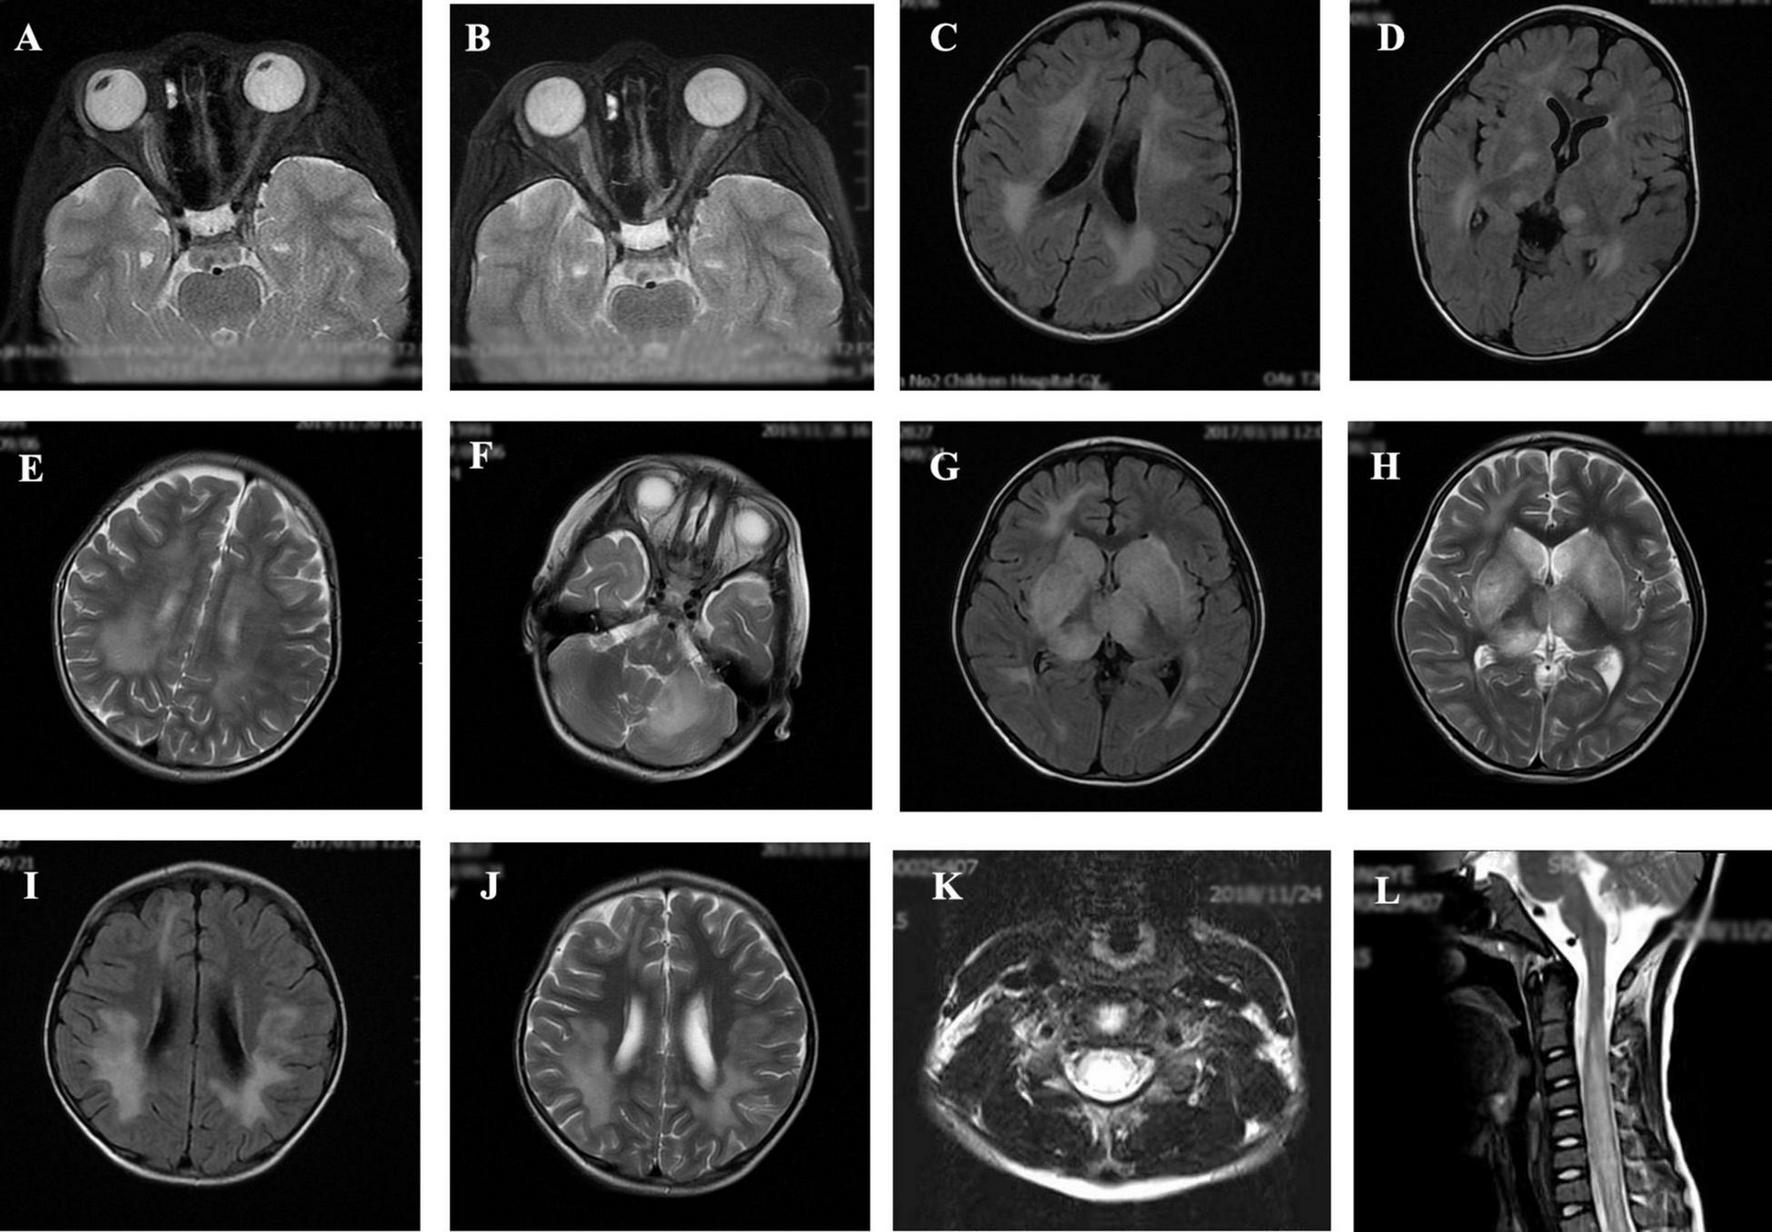

The MRI characteristics of the brain and spinal cord imaging are summarized in Table 3 and typical MRI scans of five children are shown in Figure 2. Children with MOG-IgG seropositive ADEM presented with more lesions in the thalamus and cortical area than children with MOG-IgG seronegative ADEM, and this difference was significant (p < 0.05).

FIGURE 2

Magnetic resonance imaging (MRI) results of acute disseminated encephalomyelitis (ADEM) children with or without myelin oligodendrocyte glycoprotein-immunoglobulin G (MOG-IgG. (A,B) (T2-axial) cerebral MRI of a 7-year-old boy with MOG-IgG seropositive ADEM showed small and blurred lesions of optical nerve. (C–F) [T2-axial, fluid-attenuated inversion recovery (FLAIR)-axial] cerebral MRI of a 2-year-old girl with MOG-IgG showed large, blurred lesions in bilateral white matter areas of frontal, parietal, and temporal lobes, bilateral basal ganglia, bilateral thalamus, and left cerebellar hemisphere. (G,H) (T2-axial, FLAIR-axial) cerebral MRI of a 4-year-old boy without MOG-IgG revealed a lesion in bilateral basal ganglia, thalamus, periventricular white matter, and right frontal lobe. (I,J) (T2-axial, FLAIR-axial) cerebral MRI of a 4-year-old girl with MOG-IgG seronegative ADEM showed large and blurred lesions in bilateral white matter areas of the frontal parietal. (K,L) (Sagittal-T2) Spinal MRI of a 2-year-old girl with MOG-IgG revealed prominent involvement of cervical and thoracic spinal lesion (≥3 segments).